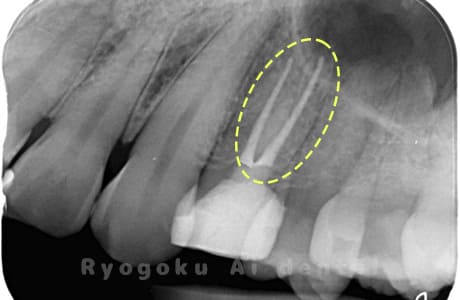

Case02

- 原因

- 慢性根尖性歯周炎

- 治療期間

- 3ヶ月

- 治療内容

- マイクロエンド

- 治療費用

- 121,000円

噛むと痛みが出る、とのことで来院した患者様です。他院での根管治療を終えてましたが、根尖病変を認めるため、マイクロエンドを行いました。

<リスク・副作用>

術後は痛み、腫れ、痺れなどの副作用が生じる場合があります。症状が再発する可能性があります。